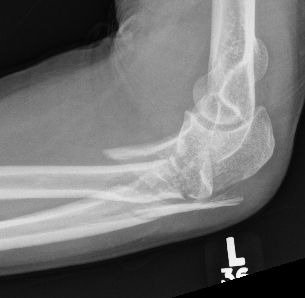

Simple Monteggia fracture - dislocations

Definition

Proximal ulna / olecranon fracture

- posterior radial head dislocation most common in adults

- no fractures

Classification

Bado Type II most common in adults with posterior radial head dislocation